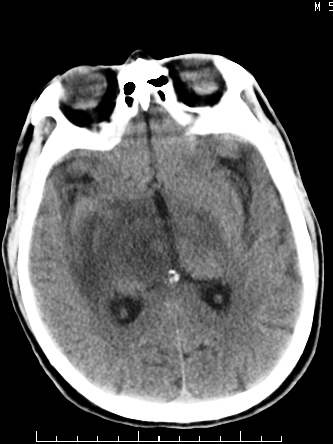

m/50,头昏头痛1月,近3天感觉左半肢体活动不利,自述半年前呈患肺tb,腰穿脑脊液未见特殊改变。现做头颅ct请大家会诊。

结核性脑膜炎,结核瘤,梗塞灶三症并存,提示颅内结核感染可能性大。

感染性病变;脑干脓肿(脓肿壁形成期),基底节及内囊(脑炎期)。顺便问一句,该病人是不是抵抗力很差,有没有糖尿病。

右侧基底节区缺血性脑梗塞.脑干区考虑结核.

可考虑结核,患者水肿范围大,囊性病灶边缘密度较高,不考虑胶质母细胞瘤